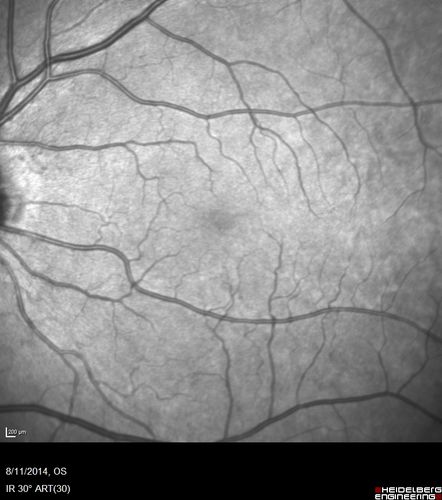

Cystoid Macular Edema following Cataract surgery and vitrectomy for floaters

73 year old woman who had decreased vision 4 months following combined vitrectomy and cataract surgery.  VA 20/63 improved in 1 month to 20/25 with ketorolac and prednisolone drops.